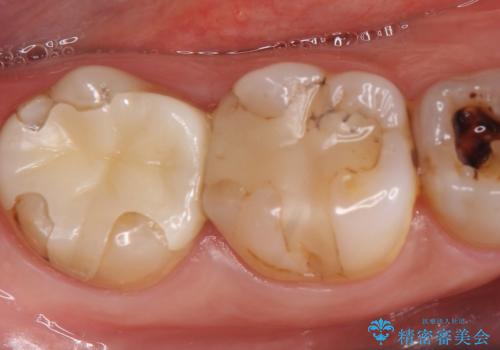

40代女性 根尖孔外感染歯のセラミック修復①

「左上2番目の歯が矯正治療後に後戻りを繰り返す」ということで、セラミック修復を希望されました。

レントゲンを撮影すると、非常に大きな病変が発覚したため、通法に従い根管治療を行った後セラミックを製作しました。

被せものの種類:ジルコニアオールセラミック スペシャル